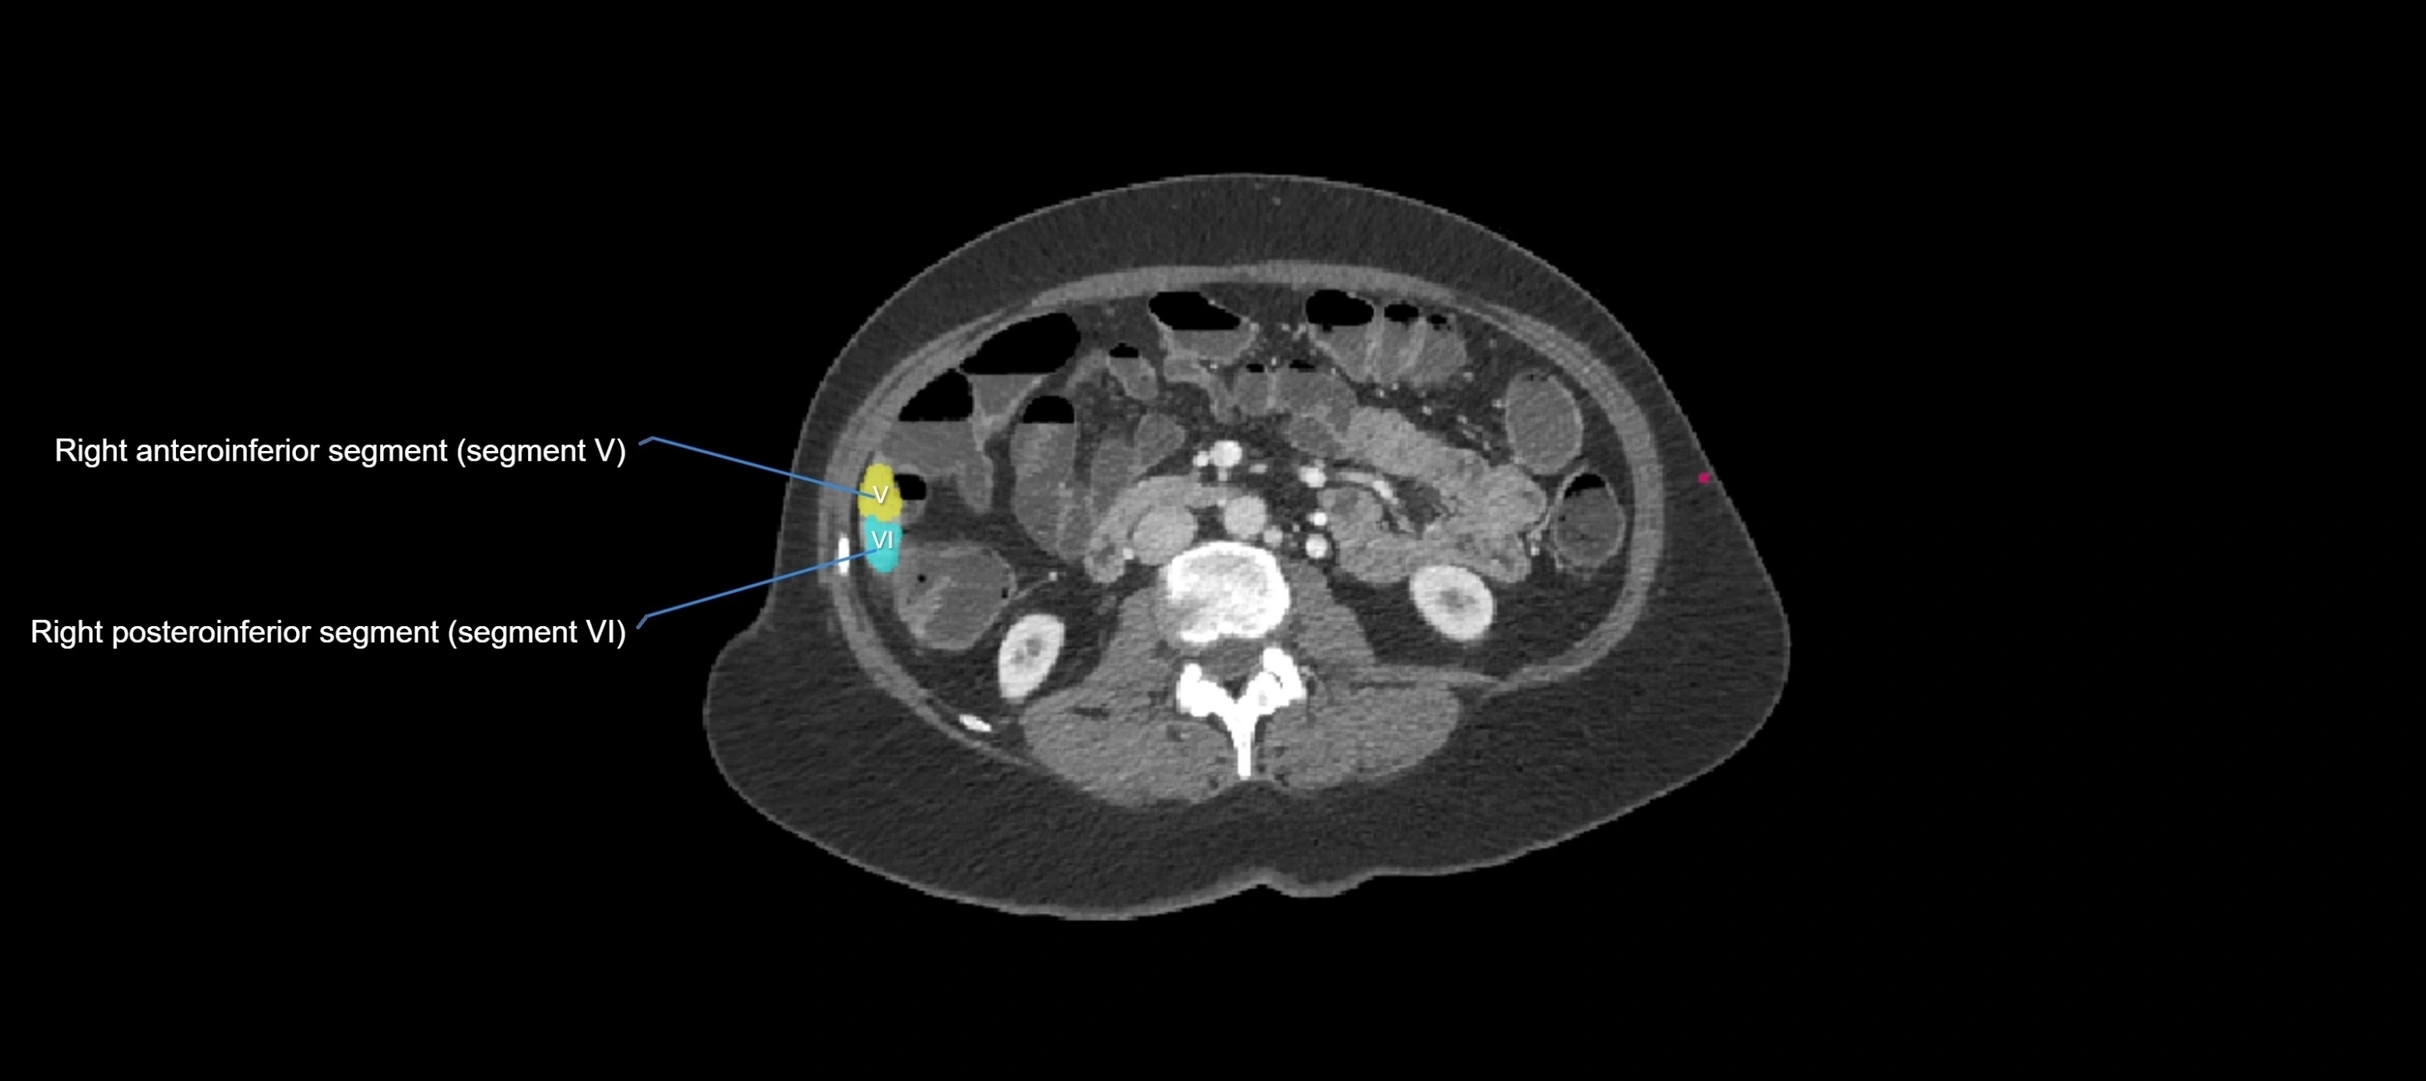

The caudate lobe of the liver is a distinct anatomical subdivision of the liver, designated as segment I in Couinaud’s classification. It lies on the posterior surface of the liver, between the fissure for the ligamentum venosum (left boundary) and the groove for the inferior vena cava (IVC) (right boundary). Superiorly, it is related to the posterior liver surface, and inferiorly it is separated from the left lobe by the porta hepatis.

CT Appearance

CT Pre-Contrast:

• Caudate lobe appears as a soft-tissue density, isodense to the rest of the liver

• Enlargement may be appreciated in cirrhosis or Budd–Chiari syndrome

CT Post-Contrast:

• Homogeneous enhancement in the portal venous phase, similar to rest of liver

• Independent venous drainage into the IVC may be visualized

• Lesions follow characteristic CT enhancement patterns (HCC: arterial hyperenhancement with washout; hemangiomas: peripheral nodular enhancement with centripetal fill-in)

CT Venous Phase (functional significance):

• Caudate lobe often enhances relatively more than other lobes in Budd–Chiari syndrome, due to preserved venous outflow

CT Image